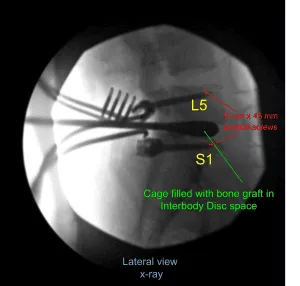

Then 40 mm x 6 mm of pedicle screws (Depuy Synthes) were inserted on either pedicle of S1 and checked under fluoroscopy and found to be in satisfactory position. Similarly, a pilot hole was made with the use of drill on either side of the pedicle of L5 followed by a gearshift to find the path under fluoroscopy. A ball-tipped probe was again used and all the walls were found to be intact. Again, tapping was done and 6 mm x 45 mm pedicle screws were inserted in either pedicle.

A trial cage was inserted and checked under fluoroscopy and it was decided to put a 9 mm x 36 mm titanium cage. Allograft was used and mixed with morselized auto bone graft of the lamina and spinous process. The cage and disc interspace was filled with bone graft and the cage was inserted and checked under fluoroscopy, found to be in satisfactory position.

Postoperative X Ray showed there is a normal lumbar lordosis. There were no destructive abnormalities or fractures. The intervertebral disc spaces appear preserved. There was no spondylolisthesis. The facet joints appear unremarkable.